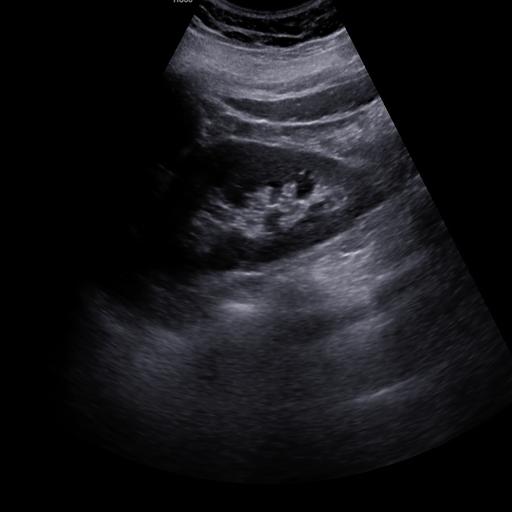

数据样例

正常肾脏样例